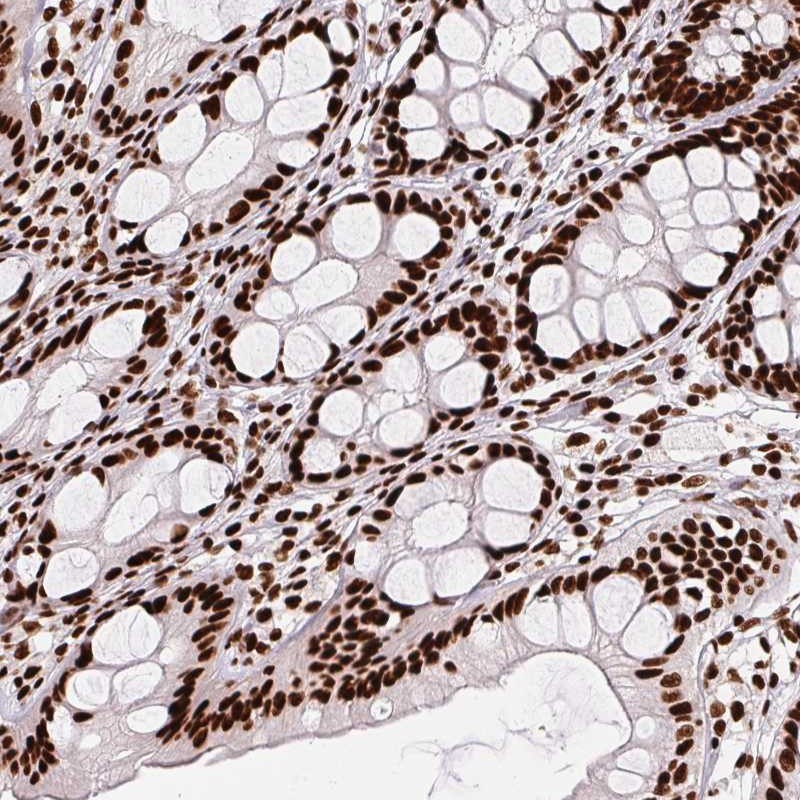

Immunohistochemical staining of human colon shows strong nuclear positivity in glandular cells.